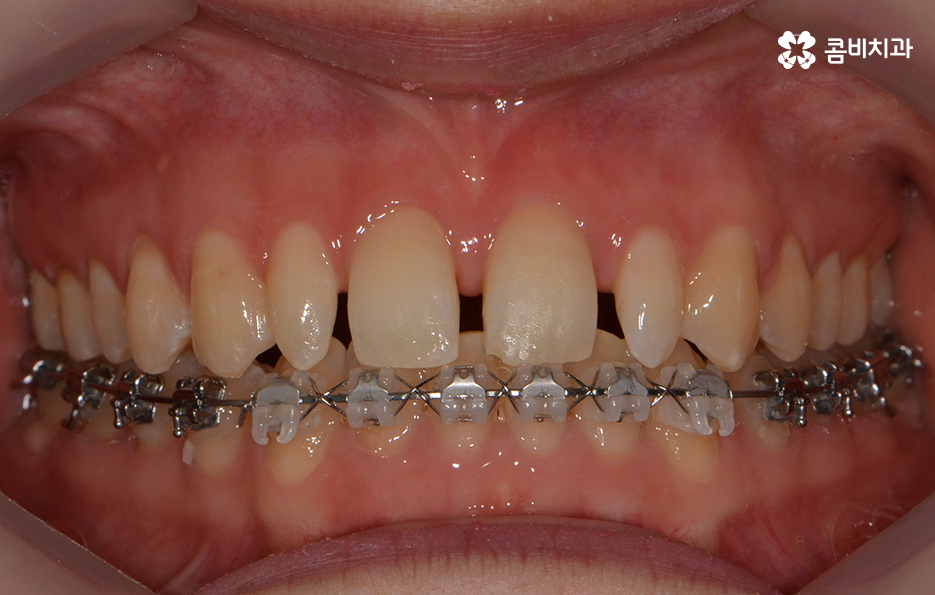

치열이 가지런하게 정렬이 된 상태에서 앞니 깨짐,

왜소치에 대해서 올세라믹이 진행되었습니다.

올세라믹은 세라믹 보철물로 치아 전체를 덮어 씌우는 방식으로

치아의 색과 모양은 물론 자연스러움을 위한 투명성까지도

갖추고 있으며 내구성도 높은 편이기 때문에 앞니가 깨졌거나

심한 변색, 충치, 왜소치 등의 치료에 많이 쓰입니다.